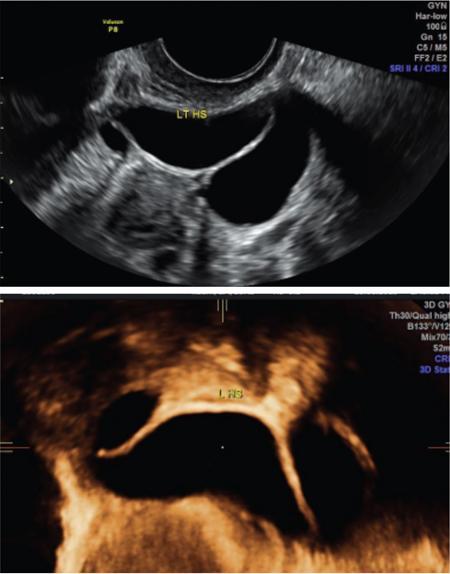

John De Lindsay, Subhashree C SALPINGITIS Salpingitis refers to the diffuse inflammation of the fallopian tubes and can be unilateral or bilateral. It is the most common early form of PID. Salpingitis has the highest risk of infertility and ectopic pregnancies. Coexisting endometritis can be seen in up to 70%–90% of nonobstetric patients. The clinical presentation in salpingitis can be variable, from being asymptomatic to severe pelvic discomfort and tenderness. Poor correlation is often noted between the degree of symptoms and the extent of tubal inflammation. In salpingitis, the fallopian tubes become hyperemic and swollen due to inflammation. With suppurative salpingitis, the lumen of the tube distends with pus and spills over into the peritoneal cavity, coating the serosa of the adjacent uterus and ovary. US maybe used as the first-line imaging modality for evaluating suspected salpingitis. Subtle abnormalities such as fallopian tubal tenderness with tortuosity, increased wall vascularity and tubal thickening of more than 5 mm may be considered pointers towards salpingitis. Salpingitis may be considered on CT when the fallopian tube thickening is more than 5 mm in axial dimension with enhancing walls (Fig. 11.17.1.1). Adjacent peritubal free fluid or cul-de-sac fluid may be other indicators. Fallopian tube thickening is the most specific sign to arrive at a diagnosis of salpingitis (Fig. 11.17.1.1). Chronic salpingitis may present as diffuse tubal irregularity with narrowing or complete obliteration of the tubes. Salpingitis isthmica nodosa is a benign inflammatory process causing nodular scarring of the fallopian tubes. At hysterosalpingography, tubal irregularity and subcentimetric protrusions from the isthmic portion of the tube are seen. PELVIC INFLAMMATORY DISEASE Pelvic infection is one of the most frequent cause of pelvic pain in females. Diagnosis of pelvic inflammatory disease (PID) can be challenging because it mimics other abdominal and pelvic processes. Pelvic ultrasonography is the first line investigation of choice. Multimodality imaging with CT and MRI are required for making a definitive diagnosis and for assessing the extent of disease and complications. PID is a spectrum of disease where microorganisms cause an inflammatory continuum ascending from the lower genital tract to infect the uterus, fallopian tubes, ovaries and may extend to the peritoneal cavity. The infection begins with cervicitis and progresses to endometritis, salpingitis, pyosalpinx, tubo-ovarian complex and ultimately tubo-ovarian abscess (TOA) (Fig. 11.17.2.1). One-third to one-half of cases are due to chlamydia trachomatis or Neisseria gonorrhoeae. However, PID is most commonly (30%–40%) a polymicrobial infection and substantial proportion of cases are nongonococcal and nonchlamydial in origin. It may be due to vaginal flora, anaerobic gram-negative rods and Mycoplasma bacteria. Tuberculosis and actinomycosis occur less frequently. Risk factors for PID include young age, multiple sexual partners, an increased frequency of coitus and the presence of intrauterine contraceptive device. Secondary infection of adnexa from gastrointestinal origin like appendicitis and diverticulitis is also common. Clinical diagnosis of acute PID often presents a challenge due to overlap of symptoms and signs with conditions like endometriosis, appendicitis and ectopic pregnancy. Symptoms: Pelvic pain is the most common symptom, although may be absent or mild in some patients. Mucopurulent vaginal discharge and fever are the other usual symptoms. Signs: Per vaginal examination reveals cervical motion tenderness, uterine and adnexal tenderness. Chronic PID symptoms: Patients may be asymptomatic. They can present with chronic pelvic pain, low back ache, dyspareunia, abnormal vaginal bleeding and vaginal discharge. WBCs on saline microscopy of vaginal secretions, elevated ESR, CRP and leucocytosis. A delay in treatment of PID causes significant reproductive and gynaecologic morbidity, such as infertility, increased risk of ectopic pregnancy, chronic pelvic pain and recurrent infection. Hence there is need for proper and adequate treatment of this condition. Most patients can be treated as out-patients with broad spectrum antibiotics. Hospitalisation is required in severe cases like TOA (Fig. 11.17.2.2). Inflammation of uterine cervix. May be infectious or noninfectious. Infectious cervicitis represents early presentation of PID. USG shows an enlarged cervix and hyperaemic cervical canal. CT and MRI show an enhancing endocervical canal. Cysts can be seen lining the endocervical canal. Cervical stroma is usually intact. Differentiation from cervical malignancy is made by lack of enhancing solid components in the abnormal cervix. Inflammation of the endometrial lining of uterus. Usually occurs during pregnancy or postpartum state or gynaecologic instrumentation. USG imaging findings depend on stage of PID. In early or mild infection, the findings are nonspecific. Endometritis may not exhibit any sonographic findings. A fluid-filled endometrial cavity is suggestive of endometritis in the setting of fever, vaginal discharge and uterine tenderness on physical examination. Intrauterine fluid is a nonspecific finding. Gas in the endometrial cavity will appear as foci of increased echogenicity with posterior dirty shadowing. Presence of gas increases the possibility of infection, though gas in the endometrial cavity can be present postpartum and postinstrumentation. Fluid in cul-de-sac is again a nonspecific finding. Internal echoes within the fluid could suggest infection (or haemorrhage) (Fig. 11.17.2.3A).